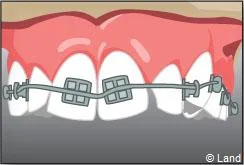

Il s’agit d’un appareil multi-attaches appelé communément « bagues ». Il permet de déplacer très précisément chaque dent. Chaque dent est équipée d’une attache appelée « bracket ». Les dents vont être mobilisées par l’utilisation de fil métallique dont l’alliage, la section, la forme sont déterminés par les différentes étapes du traitement. Ils seront insérés dans les attaches par le biais de ligatures élastiques, métalliques ou d’un mini-clip. Les « brackets » utilisés chez les adolescents sont la plupart du temps métalliques mais ils peuvent être remplacés avantageusement par des éléments transparents ou de la couleur des dents.